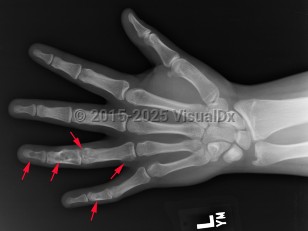

Enchondroma in Adult

Ollier disease and Maffucci syndrome are nonhereditary conditions that present as multiple enchondromas. Ollier disease involves multiple asymmetric enchondromas of the digits. It is most commonly seen in childhood. These slow-growing tumors usually stop growing after puberty, but masses can create deformity and limb asymmetry. Pathologic fractures may be seen. Ollier disease has a 15%-20% risk for secondary chondrosarcoma.

Prevalence: Enchondroma is a latent lesion that comprises 15%-25% of cartilage tumors. It is the most common hand tumor, accounting for 90% of cases. Enchondroma usually presents in the third and fourth decades of life and occurs equally between both sexes.

Pathophysiology: Enchondroma pathophysiology is believed to involve incomplete endochondral ossification in which physeal remnants become entrapped in the medullary cavity of the metaphysis and proliferate. In the hand, enchondromas are typically diagnosed after a pathologic fracture. Elsewhere, they are typically an asymptomatic incidental finding on x-ray or advanced imaging performed for other reasons. Pain is usually due to a nearby abnormality rather than the tumor itself.